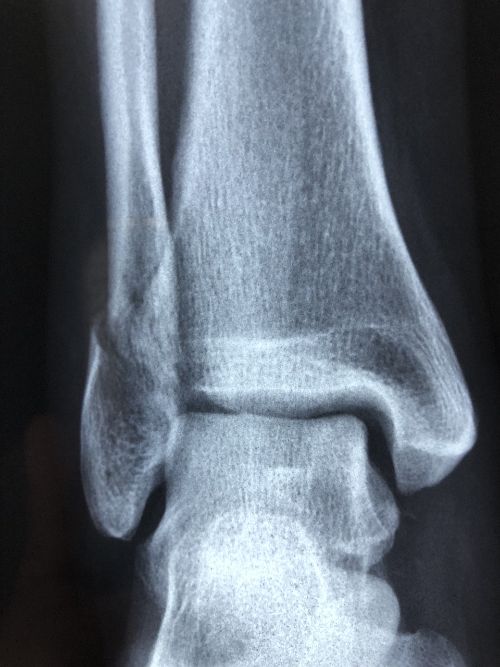

Le centre est équipé d’une radiologie standard, permettant le diagnostic rapide des traumatismes et des pathologies ostéo-articulaires. Les échographies diagnostiques sont assurées sur rendez-vous par le Dr Yannick Lebreton, du Centre Radiologique de la Glâne, garantissant un accès direct à l’imagerie de haute qualité.